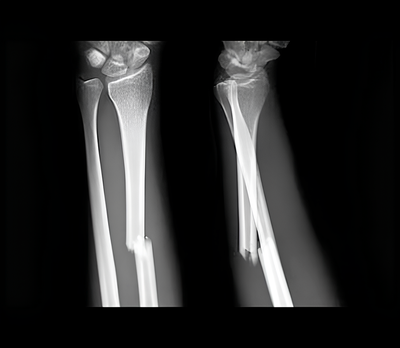

Согласно медицинской классификации, существуют абсолютные и относительные признаки перелома.

Абсолютные признаки (точно указывают на перелом):

Патологическая подвижность

Неестественное положение конечности

Костный хруст при движении

Видимые костные отломки (при открытом переломе)

Относительные признаки (позволяют заподозрить перелом):

Боль при нагрузке

Отечность в месте повреждения

Гематома

Ограничение подвижности